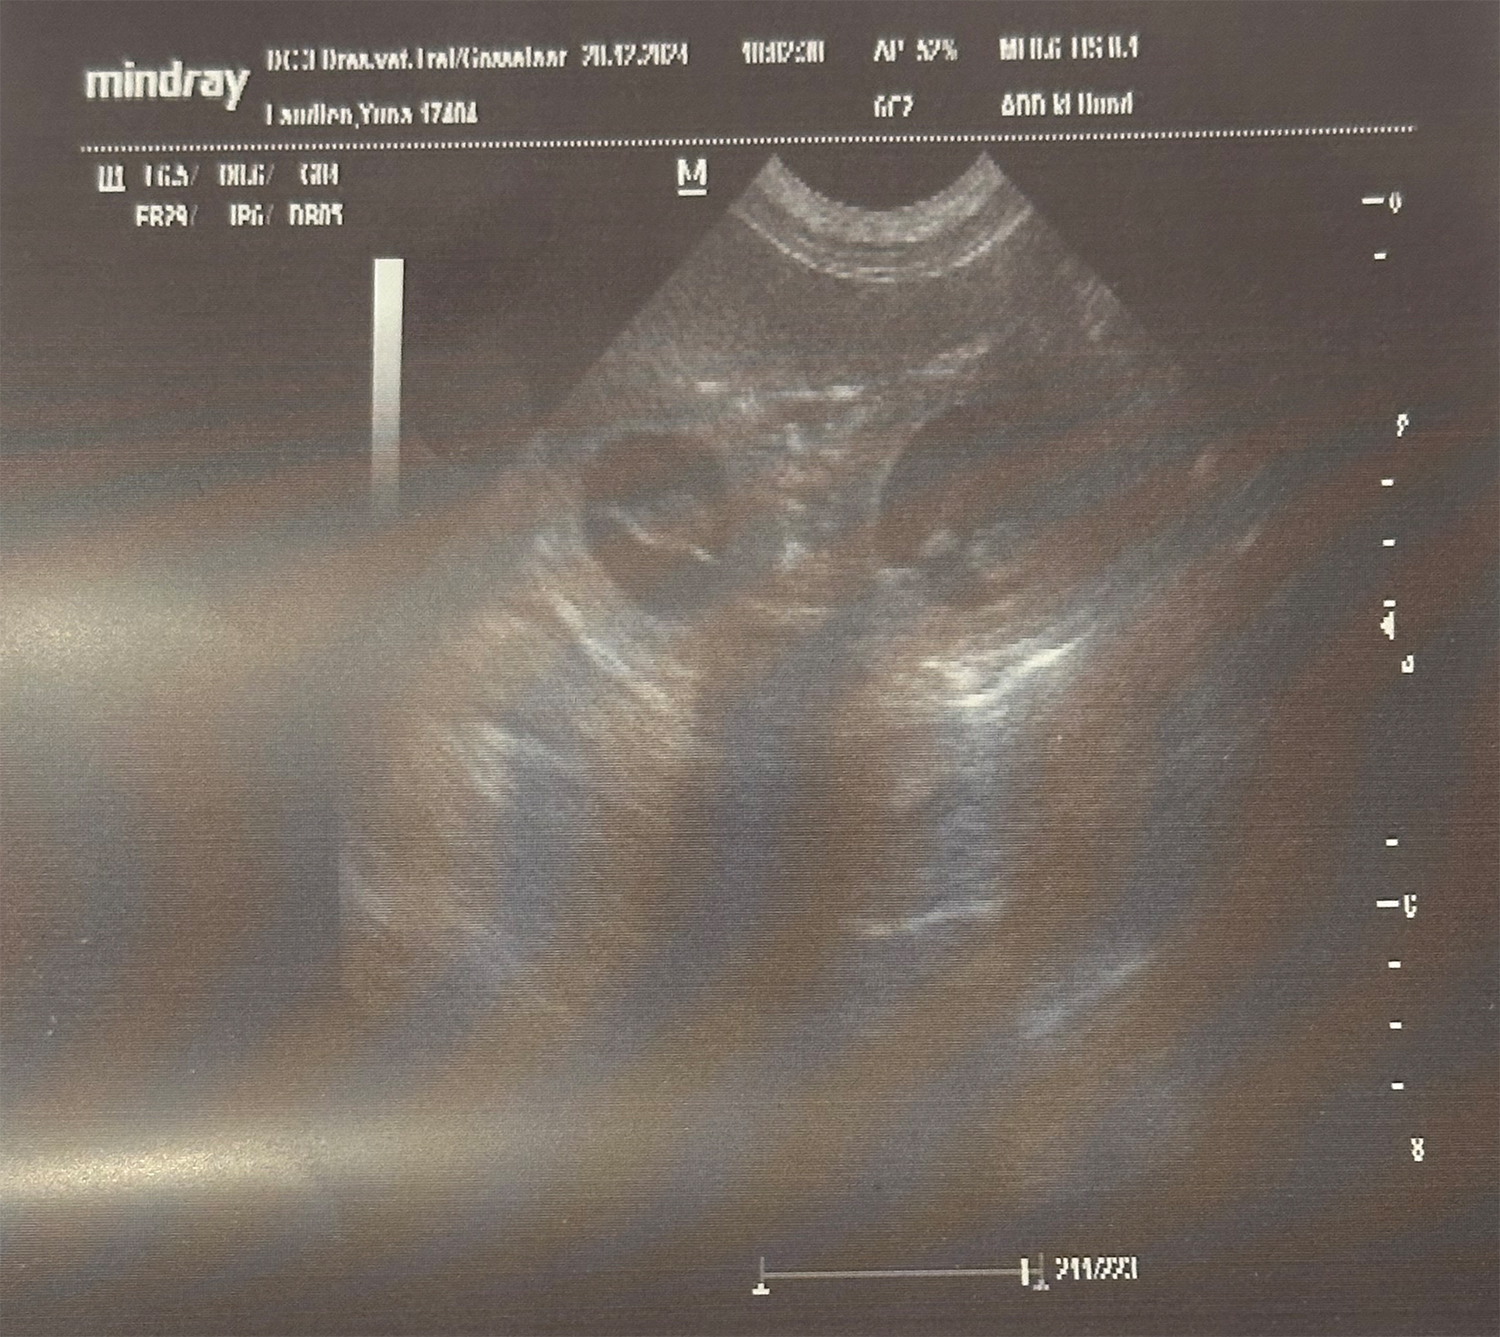

Heute waren wir nochmal zu einer kleinen Ultraschall-Kontrolle bei unserer Tierärztin.

Frau Dr. Gosselaar wollte sich vergewissern, ob die Mäuse weiterhin so schön gedeihen und jaaaaa sie sind ordentlich gewachsen, die Beinchen waren zu erkennen, die Herzchen waren schön am schlagen und sie waren aktiv am strampeln.

Das alles zu sehen war doch ziemlich emotional und wir freuen uns jetzt noch mehr auf die Zwergenbande.

Hatte Yuna Mitte Februar beim Tierarzt 31,6 Kilogramm auf die Waage gebracht, waren es am heutigen Tage schon 33,6 Kilogramm.

Mehr Futter (Welpenfutter) bekommt Yuna seit gestern... und was soll ich sagen, Yuna ist schwer begeistert vom neuen Futterplan.